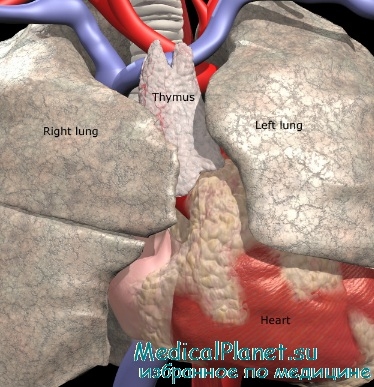

Фотографии вилочковой железы тимуса: структура и функции